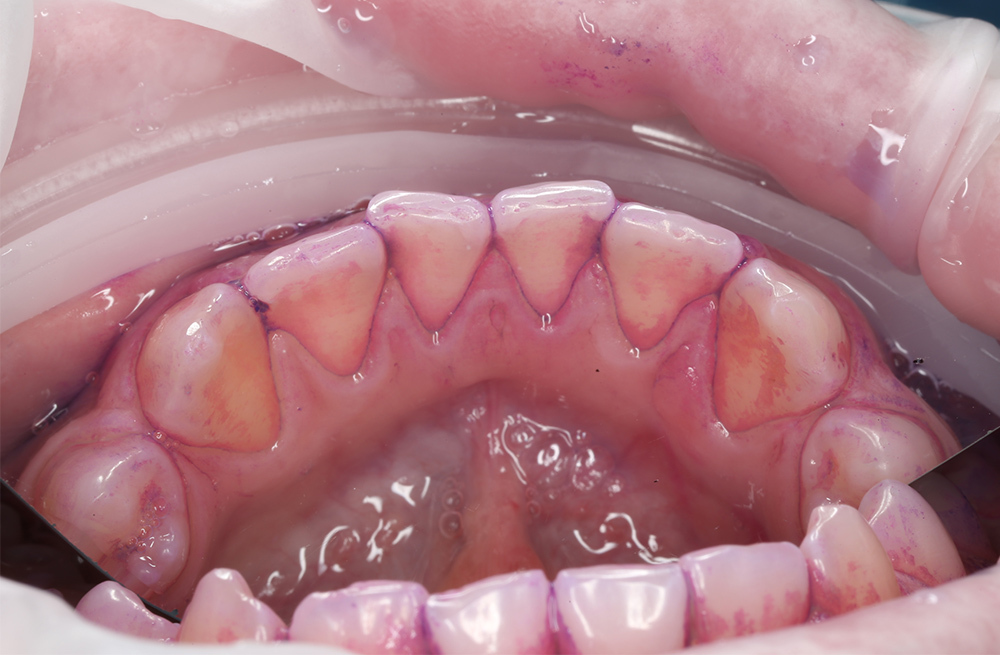

Удаление мягкого и пигментированного налёта у подростка с использованием Air-flow

Эффективная чистка зубов с ортодонтическими конструкциями под контролем стоматолога

Детская чистка зубов с профессиональным уходом ребёнку 10 лет

Чистка зубов Air Flow у ребёнка для профилактики кариеса

Профессиональная гигиена и обучение домашнему уходу за зубами с помощью технологии Air Flow

Первая профессиональная гигиена полости рта у ребёнка с использованием Air Flow

Профессиональная чистка зубов Air Flow с диагностикой и планированием лечения кариеса

Плановая стоматологическая гигиена для подростка 12 лет

Профессиональная чистка зубов подростку 13 лет

Профессиональная чистка зубов с ретейнерами подростку 14 лет